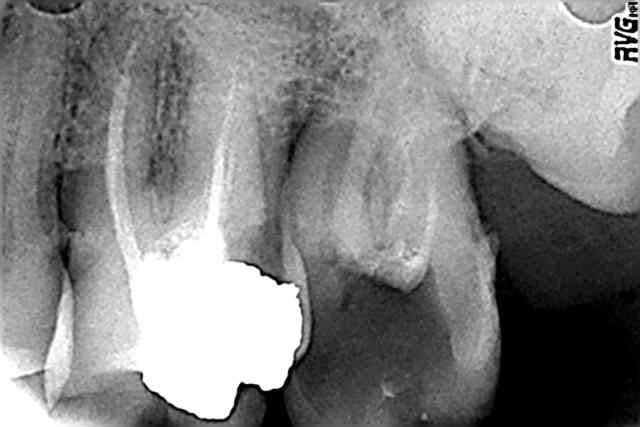

Bon je sais que le fil est lancé sur la mixte, mais comme aujourd'hui j'inaugure le thermaprep qu'un (très) gentil confrère m'a prété, voilà ma première obturation au thermafill. Je sais que sur le plan paro cette dent n'a pas beaucoup d'avenir mais bon... Qui ne tente rien ne tente rien, hein ?

Question: vous la mettez où la pâte ? sur le tuteur en sortie de four ? Dans le chambre (au risque de rien voir ?)

superbe endo pour un premier essai au thermafill

(moi ma premiere en bouche je l'avais bien merdée a cause de la proximite des canaux)

Pour la pâte,je la mets avec un cône de papier un autre truc, avec une lame de bistouri je vire la gutta du thermafill qui ne rentrera pas dans le canal pour eviter que les autres canaux soient noyés

et pour finir faire super gaffe de virer le spray sur la turbine quand tu utilise le thermacut